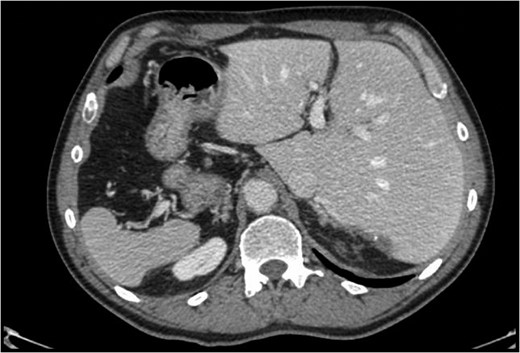

Situs inversus totalis (SIT) is a congenital condition consisting of a mirror image of transposition of the abdominal and thoracic organs occurring in about 1:5000 to 1:10 000 adults. We report on a 60-year-old male with a single colorectal liver metastasis in the Segment 7. The patients underwent a totally laparoscopic sub-segmentectomy. Intraoperative approach on a reverse posterior segment was difficult because of left-sided position of the liver. Postoperative course was uneventful and the patient was discharged after 5 days. To our knowledge, only a few cases of open liver resections in patients with SIT have been published. This is, therefore, the first case of laparoscopic liver resection for colorectal liver metastasis in a patient with SIT. We provide the readers with useful tips to perform minimally invasive liver surgery in such patients.

Situs inversus is a congenital condition with an incidence ranging between 1:1000 and 1:10 000 characterized by left-to-right transposition of one or more normally asymmetrical organs of the body. Situs inversus totalis (SIT) consists of a mirror-image transposition of the abdominal and thoracic viscera, which occurs in about 1:5000 to 1:10 000 adults [1]. Patients affected by SIT are usually completely asymptomatic, but they have more commonly major defects which can shorten their lifespan [1].

As usual, we performed an intraoperative ultrasonography with the mode of scanning was switched from normal to reverse modality; so, it was possible to have on the screen the usual appearance of the intrahepatic anatomy despite of the present specular anatomy. This trick was very useful to reach a good resection line.

These observations are even more true for a patient with previous open surgery and an SIT with the double challenge related to the anatomic position of the liver and the posterior (7) segment involved. Another challenging maneuver was the separation of the liver from the diaphragm; the absence of any ligament made this part of the procedure very demanding to identify the correct plane from the diaphragm and the liver and minimize the bleeding.